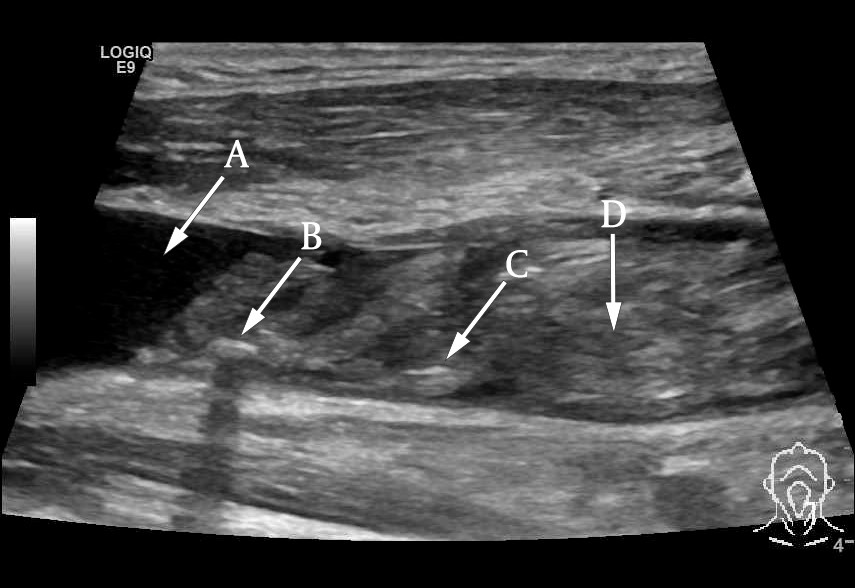

However, ultrasound examination of the neck showed a significant thrombotic mass that almost completely occluded the left internal jugular vein and subclavian vein (Figures 1 and 2). The total extent of the thrombus could not be determined using ultrasound, and therefore CT venography was performed in addition. This revealed extensive thrombosis involving the lower part of the left jugular vein (from the level of the carotid bifurcation), subclavian vein and brachiocephalic vein up to the inlet of the superior vena cava (Figure 3). Multiple air bubbles were dispersed throughout the thrombotic mass. We suspected that these were caused by bacteria, and that the thrombus was thus the focus of the patient's infection.

Ultrasound is a non-invasive and cost-effective method for detecting thrombotic masses. Unfortunately, however, it is suboptimal for diagnosing thrombi located deep below the mandible or clavicle. For this reason, CT venography is preferred by many (6). In our case, CT venography allowed us to determine the extent of the thrombotic mass and also revealed the characteristic air bubbles that strengthened suspicion of an infected thrombus.